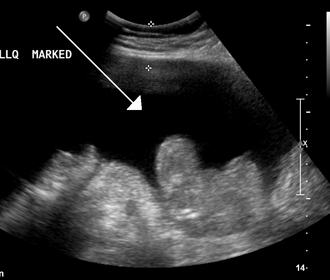

- Ultrazvuk: Manja količina se ovim pregledom može vidjeti ispod jetre ili u Douglasu. G

- Punkcija trbušne šupljine (može biti ultrazvučno navođeno) za uzimanje uzorka tekućine za analizu